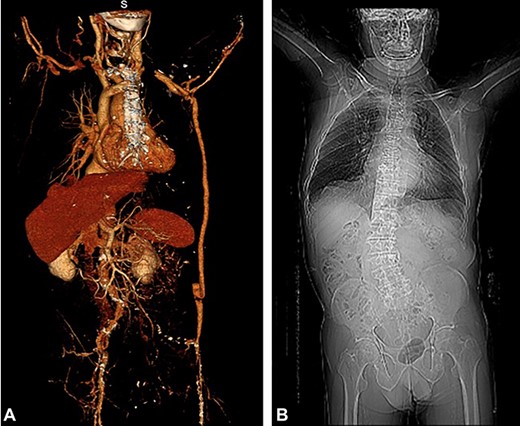

An 85-year-old male, whose background includes: (i) revascularized ischemic heart disease (January 2010), but with subsequent stress angina, and (ii) axillary-femoral bypass (AxF) (July 2018) with a Dacron prosthesis (8 mm in diameter, without external support) due to critical ischemia of the left lower limb secondary to occlusion of the left iliac arterial axis. Twenty-two months after carrying out the AxF, the patient abruptly presented, without prior trauma, with a lump at the level of the abdominal path of the AxF; a mass of 5 cm in diameter could be seen that beats and did not alter the surrounding skin. Patent femoral and popliteal pulses were noted. The patient had an ABI of 0.75. A Doppler ultrasound yielded an image showing a permeable prosthesis and graft angulation. The CT scan confirmed kinking of the prosthesis (Fig. 1). Under general anesthesia, the redundant prosthetic segment was resected and replaced, over a 20-cm section, by a new Dacron-silver prosthesis in the terminal–terminal position. Postoperatively, the patient has so far experienced without no incidents (ABI = 0.80). A microbiological culture taken from the prosthesis was negative. The patient consent to publish their case details and images was obtained.

The exact correspondence between the length of the AxF and the size of the patient’s body can change during the postoperative period. On the one hand, excessive weight gain in the patient’s body can make the graft relatively short [3]. On the other hand, multiple fractures of the lumbar vertebrae can lead to a significant shortening of stature [4] or, as in the case of our patient, the development of serious scoliosis (Panel A-2); angulation of the prosthesis facilitates skin ulceration, thrombosis and graft contamination [4].